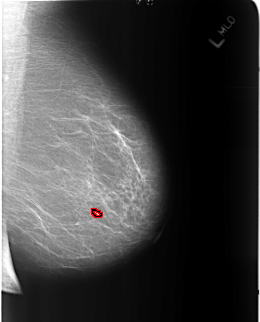

B_3211_1.LEFT_MLO

LEFT_MLO LINES 5152 PIXELS_PER_LINE 4152 BITS_PER_PIXEL 12 RESOLUTION 50 OVERLAY

FILE: B_3211_1.LEFT_MLO.OVERLAY

TOTAL_ABNORMALITIES 1

ABNORMALITY 1

LESION_TYPE CALCIFICATION TYPE COARSE DISTRIBUTION N/A

LESION_TYPE MASS SHAPE OVAL MARGINS CIRCUMSCRIBED

ASSESSMENT 2

SUBTLETY 5

PATHOLOGY BENIGN_WITHOUT_CALLBACK

TOTAL_OUTLINES 1

BOUNDARY